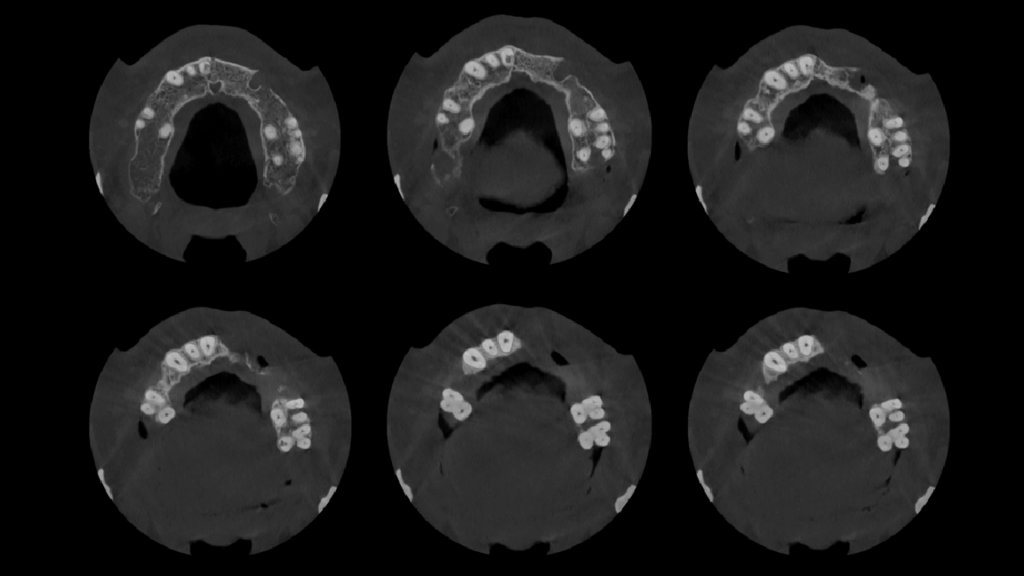

A la evaluación de la tomografía cone beam de campo mediano (FOV = 10 x 10) se observa en la pieza 11 la presencia de una imagen hipodensa de forma irregular localizada a niel de tercio medio radicular y que se compromete la dentina radicular por mesial y palatino, asimismo se observa la pieza 27 que además de la restauración presenta una imagen hipodensa en raíz palatina a nivel de tercio medio radicular y finalmente un trazo de fractura vertical por distal que compromete la zona de furcación y ocasiona un proceso osteolítico interradicular.

CORTES AXIALES